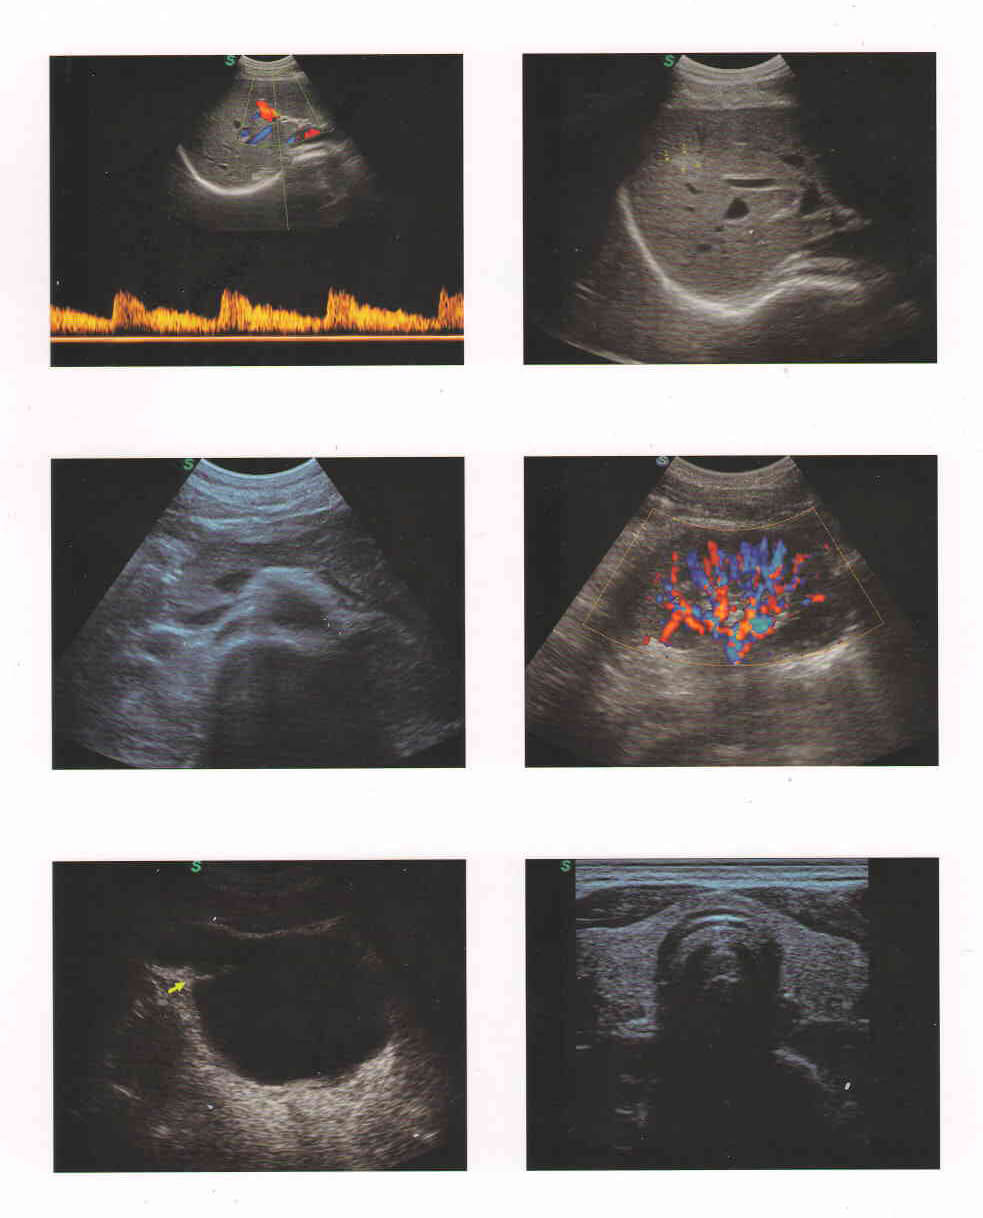

Máy siêu âm Doppler màu 4D SonoScape S11 được thiết kế với màn hình LCD có độ phân giải cao 15 inch với cánh tay khớp nối nhanh và thiết kế xe đẩy nhanh, 4 cổng cắm đầu dò hoạt động sẵn, ứng dụng trong Duplex, Doppler màu, DPI, PW Doppler, hình ảnh hài hòa mô, sp-scan đốm lốm đốm, hình ảnh toàn diện

• Duplex, Doppler màu, DPI, PW Doppler, hình ảnh hài hòa mô, giảm sp-scan đốm

Siêu âm 4D Sonoscape S11 được sử dụng cho tất cả các ứng dụng chung bao gồm: Bụng, Sản phụ khoa, Phụ khoa, Cơ xương, Thấp khớp, Mạch máu, Tiết niệu, Tim mạch…

Tương thích với tất cả các đầu dò:: Convex, linear,4D, tim, phụ khoa…

Chế độ quét 2D rõ nét, lưu lượng máu nhạy.

Công nghệ hình ảnh 3D tự do và âm lượng 4D.

Sinh thiết,được thiết kế đặc biệt có thể hướng dẫn một loạt các đầu dò 3D / 4D của bộ chuyển đổi có thể. Cho phép kết nối cảm xúc mạnh mẽ cho các chị em phụ nữ mang bầu

– Hệ thống Doppler màu đáng tin cậy,

– Công nghệ chính: Hình ảnh hợp chất không gian, Hình ảnh toàn cảnh, Giải phẫu M –Mode, hình ảnh 3D tự do, hình ảnh 4D (một số trong số đó là tùy chọn.)